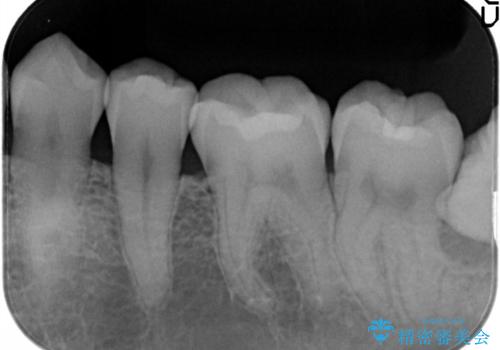

メタルフリー セラミックインレー

- メタルフリーの治療を希望されて来院されました。

セラミックインレーの治療を2回の来院で終了しております

e-max プレスインレーにて修復治療を行っているため適合性及び審美性の高い治療を行うことができます